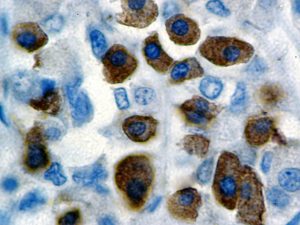

It is the ICU physician who is most likely to witness one of the deadliest manifestations of the abnormal immunological response, the cytokine storm syndrome (CSS). This response is also referred to by some as the cytokine release syndrome (CRS). CSS is characterized by continuous activation and expansion of macrophage and lymphocyte populations, which secrete large amounts of cytokines, causing the cytokine storm. This massive cytokine release is akin to hemophagocytic lymphohistiocytosis (HLH) disease, a syndrome characterized by initial unchecked and persistent activation of cytotoxic T lymphocytes and NK cells.

Clinical and laboratory manifestations of HLH include fever, enlarged liver and/or spleen, neurologic dysfunction, coagulopathy, liver dysfunction, cytopenias (i.e., low levels of erythrocytes, leukocytes, and/or platelets), hypertriglyceridemia, hyperferritinemia, hemophagocytosis, and eventually diminished NK cell activity as the immune system becomes progressively paralyzed. HLH can be familial (primary HLH) or secondary to another disease process (sHLH), such as rheumatic disease, in which it is referred to as macrophage activation syndrome (MAS, characterized by elevated ferritin).